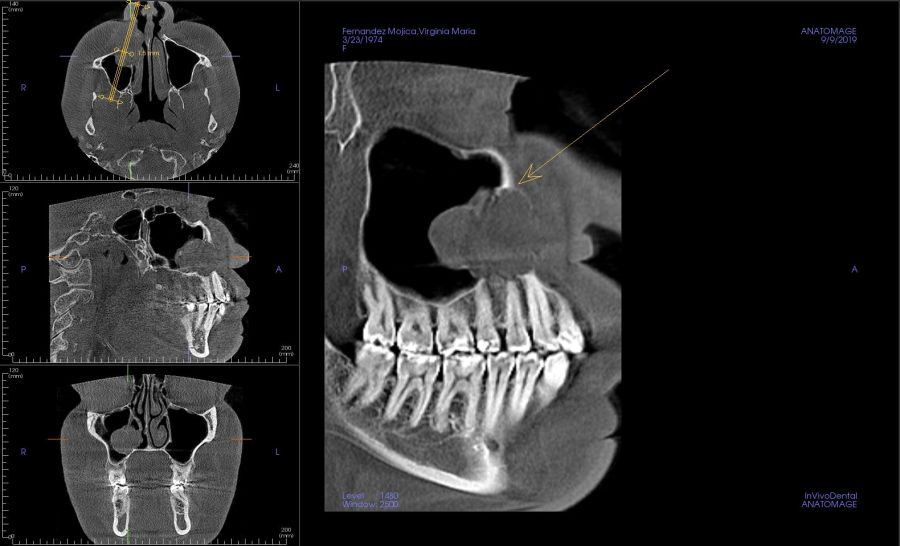

Presentamos el caso de una paciente de 47 años que acude al servicio de cirugía maxilofacial por dolor en el área sinusal derecha en Junio de 2020. Se realizó una radiografía panorámica en la que se observó una imagen sospechosa en la zona del primer cuadrante. Dichos hallazgos se confirmaron con la realización de una tomografía axial computarizada (TAC) facial y una resonancia magnética en las que se identifica una extensa lesión tumoral que ocupaba el seno maxilar derecho e infiltraba el suelo de la órbita derecha y fosa nasal derecha (Figuras 1, 2 y 3). Tras la realización de una biopsia, se confirmó la presencia de un carcinoma adenoide quístico. De este modo, se planificó la extirpación quirúrgica y la fijación mediante placas preformadas sobre un modelo impreso en poliamida (Figura 4).